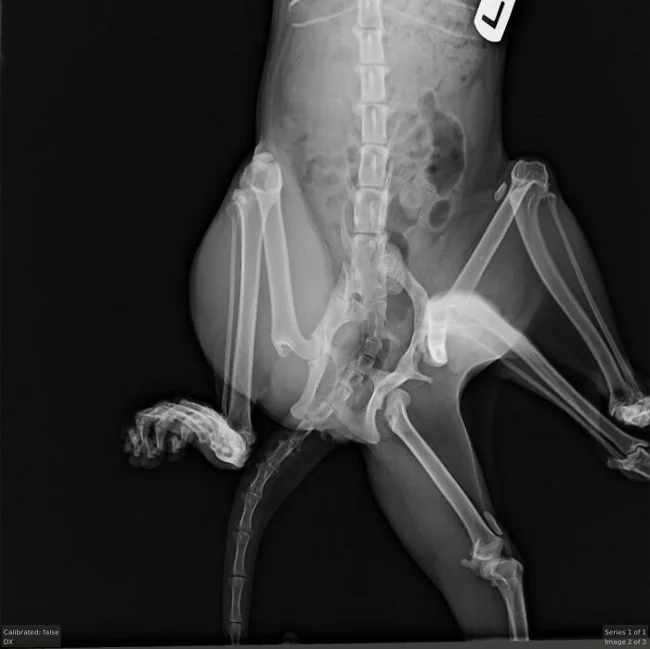

В клинике Windermere ветеринары сделали рентгеновские снимки Битси. Они решили, что операция поможет ей чувствовать себя лучше

Кошка перенесла сложную операцию по удалению лишних конечностей и таза